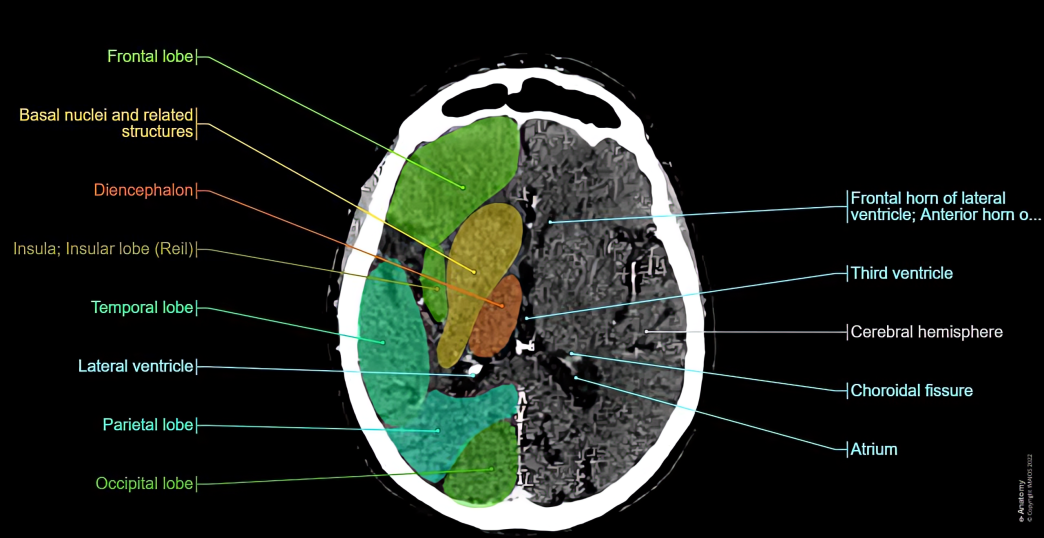

Alen Emmanuel Joshy: CT Brain in Intracranial Hemorrhage

”CT Brain in Intracranial Hemorrhage

Technical and Protocol Points:

- Non-contrast CT (NCCT) is mandatory initially — contrast can obscure acute blood.

- Thin slices (≤5 mm, preferably 1–2 mm) improve detection of small bleeds.

- Bone window helps identify associated skull fractures.

- Repeat CT is crucial in deteriorating patients to assess bleed progression.

Density and Physics Insight:

- Acute blood appears hyperdense (60–80 HU) due to high protein and iron content.

- Density reduces over time due to clot lysis and dilution by CSF.

- Hematocrit level influences bleed conspicuity on CT.

Evolution of Hemorrhage on CT:

- Hyperacute (<6 hrs): May appear heterogeneous due to active bleeding (“swirl sign”)

- Acute (6 hrs–3 days): Homogeneously hyperdense

- Early chronic: Peripheral membrane formation may be seen

Signs Suggesting Active or Severe Bleed:

- Swirl sign: Hypodense area within hyperdense clot → ongoing bleeding

- Spot sign (on CTA): Predictor of hematoma expansion

- Mass effect disproportionate to bleed size

Important Secondary Effects:

- Raised intracranial pressure (ICP)

- Herniation (subfalcine, transtentorial, tonsillar)

- Acute obstructive hydrocephalus (especially with IVH or SAH)

Etiology Clues Based on Location:

- Basal ganglia bleed: Hypertension

- Lobar hemorrhage: Amyloid angiopathy, tumor, anticoagulation

- Cerebellar bleed: Life-threatening due to brainstem compression

- Temporal lobe bleed: Consider trauma or aneurysmal SAH extension

When to Add CT Angiography?

- Suspected aneurysm or AVM

- Young patient with no hypertension

- Lobar hemorrhage without trauma

- SAH with negative NCCT after 6 hours

Pitfalls and Mimics on CT:

- Calcifications vs acute bleed

- Beam-hardening artifacts

- Contrast staining post-procedure

- Dense venous sinuses mimicking SAH

Clinical Correlation Matters:

- Sudden severe headache → rule out SAH

- Trauma with lucid interval → EDH

- Elderly with minor trauma → SDH

- Anticoagulated patients → high risk of expansion

Take-Home Message:

- CT brain not only detects hemorrhage but also predicts severity, guides management, and helps identify the cause. Early recognition saves lives.”